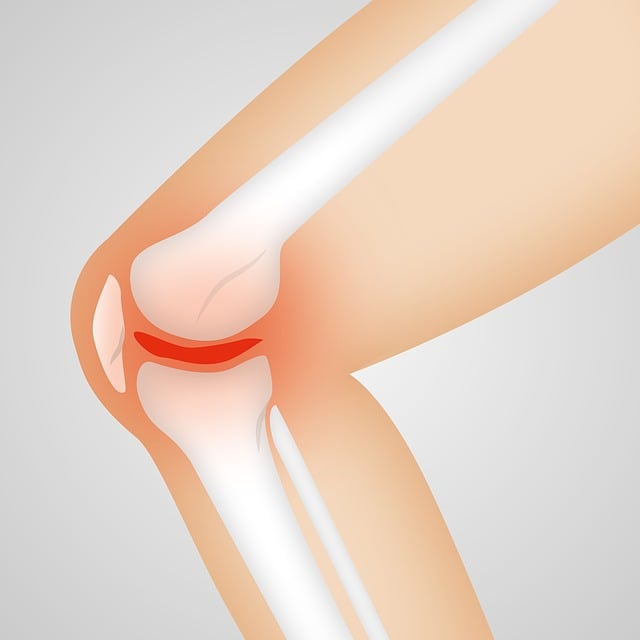

무릎 인공관절 수술은 퇴행성 관절염이나 심각한 관절 손상을 겪는 환자들에게 효과적인 치료법입니다.

무릎 인공관절 수술 후에는 합병증이 발생할 수 있습니다. 대표적인 합병증으로는 감염, 인공관절의 느슨해짐, 혈전 등이 있으며, 이로 인해 무릎 인공관절 수술 회복 기간이 길어질 수 있습니다.